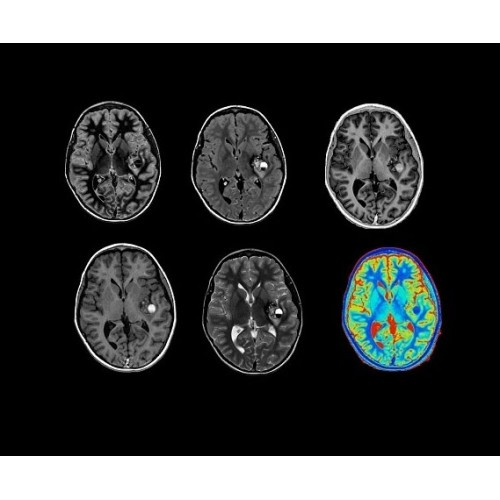

SIGNA PET/MR 3.0T — это гибридная система, в которой совмещаются две принципиально разные технологии — магнитно-резонансную томографию (МРТ) и позитронно-эмиссионную томографию (ПЭТ). Система отличающийся высокой чувствительностью и эффективностью и предназначена для диагностики в области онкологии, неврологии, кардио-васкулярных исследований, исследований воспалительных процессов.

Компания GE Healthcare представляет революционную, полностью интегрированную систему SIGNA PET/MR1, в которой сочетаются времяпролетная технология (TOF) и возможности напряженности магнитного поля 3.0 Тл. Мы поможем вам поднять исследования на более высокий уровень. SIGNA PET/MR позволяет достичь впечатляющей точности и скорости исследований, а благодаря новейшей технологии реконструкции Q.Clear2 качество изображений улучшается в два раза. Кроме того, в систему включен полный набор клинических приложений и гибких катушек для проведения любых видов исследования, открывая для вас возможности визуализации, о которых вы даже не догадывались.

Впечатляющие клинические возможности

Система SIGNA PET/MR предлагает впечатляющие клинические возможности и открывает доступ к наиболее полным пакетам программных приложений.

Новейшая платформа SIGNA Works4 повышает производительность ключевых технологий визуализации GE Healthcare. SIGNA Architect поставляется с предустановленными стандартными приложениями. Расширенные функции SIGNA Works с возможностью обновления позволят устанавливать новые приложения в соответствии с растущими потребностями вашей клинической практики.

Стандартный пакет приложений SIGNA Works позволит вам достичь желаемых результатов в клинической практике благодаря набору высокоэффективных средств визуализации. Программные приложения, входящие в состав данных клинических пакетов, включают широкий спектр контрастов, функции обработки 2D- и 3D-данных, а также возможность коррекции артефактов движения. SIGNA Works предоставляет набор инструментов, необходимых для проведения эффективного клинического исследования.

• Специальный пакет приложений для измерения и сравнения объемных изображений ЦНС с нормами поможет вам в диагностике нейродегенеративных заболеваний, а дополнительные инструменты визуализации — в постановке точного диагноза с помощью бета-амилоидов и радиоизотопных маркеров ФДГ.